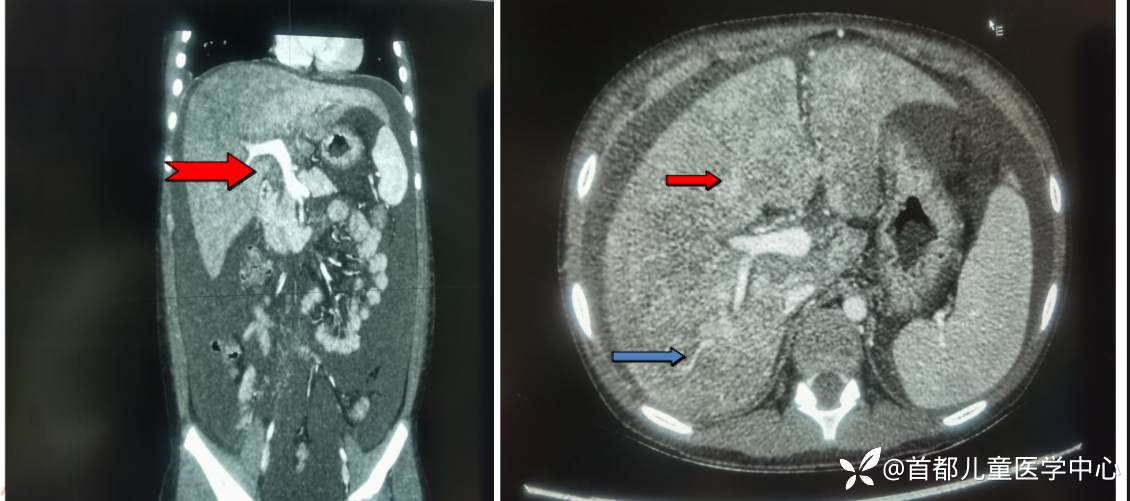

左:红色箭头:下腔静脉显示无异常

右:红色箭头:肝实质密度不均均减低,蓝色箭头:显示特征性“地图状”不均匀强化

腹部增强CT:肝实质增强后呈弥漫性明显不均匀强化,大量腹水、盆腔积液;右侧胸腔积液,右肺下叶部分受压不张;腹部皮下水肿。

HSOS是由各种原因导致的肝血窦、肝小静脉和小叶间静脉内皮细胞水肿、坏死、脱落进而形成微血栓,引起肝内淤血、肝功能损伤和门静脉高压的一种肝脏血管性疾病,临床表现为腹胀、肝脏肿大触痛、腹水、黄疸及体重增加。国内外关于HSOS的病因各不相同,在西方国家常见于骨髓造血干细胞移植前的预处理,在我国多因服用含PA植物或其他植物而致病,其中以土三七最为常见,因此这类HSOS又被称为PA相关的HSOS。PA-HSOS 在早期缺乏特异症状,多以腹胀、黄疸、乏力纳差和肝区胀痛为主要表现,其中腹水是土三七相关HSOS最常见的临床体征,增强CT特征表现为门脉期和平衡期肝脏呈“地图样”不均匀强化,肝静脉和下腔静脉多见狭窄或显示不清。